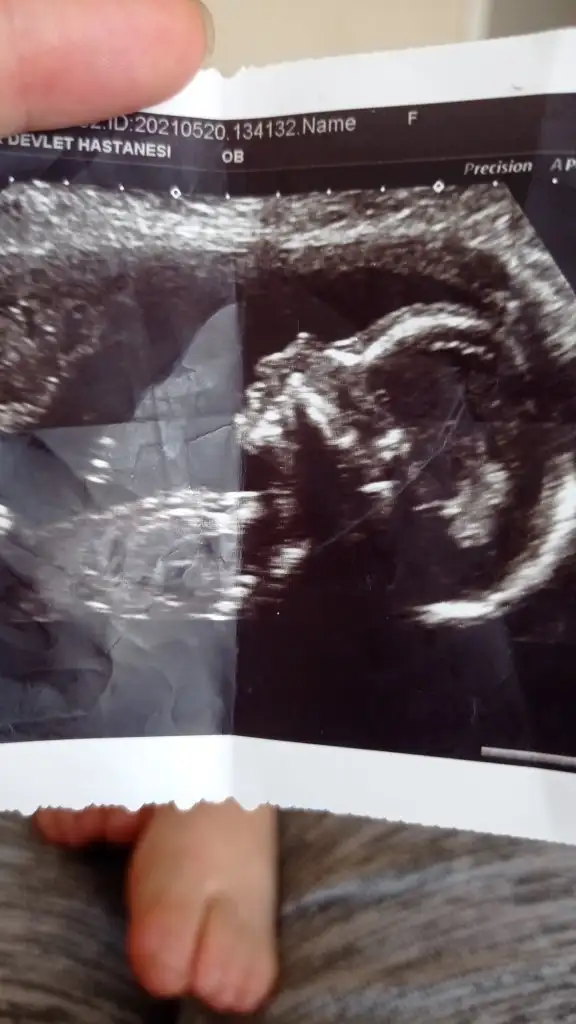

- 27 Mayıs 2021

- Konu Sahibi Karamelek45